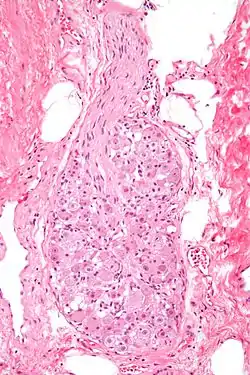

Micrograph of a ganglion. H&E stain.

A ganglion (pl.: ganglia) is a group of neuron cell bodies in the peripheral nervous system. In the somatic nervous system, this includes dorsal root ganglia and trigeminal ganglia among a few others. In the autonomic nervous system, there are both sympathetic and parasympathetic ganglia which contain the cell bodies of postganglionic sympathetic and parasympathetic neurons respectively.

Ganglia are primarily made up of somata and dendritic structures, which are bundled or connected. Ganglia often interconnect with other ganglia to form a complex system of ganglia known as a plexus. Ganglia provide relay points and intermediary connections between different neurological structures in the body, such as the peripheral and central nervous systems.